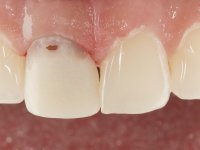

The patient came to the consultation because she did not like the “dark line next to the gums” that she had on her upper right central incisor.

Female patient, 33 years old, non-smoker. Tooth 11 with endodontic treatment rehabilitated with a crown. This crown shows an infiltrated cervical interface. The smile line was high, this area being very visible. The patient had a thick gingival phenotype and good oral hygiene.

The patient was asked to remove the infiltrated crown and make a new crown with a ceramic-coated Zr infrastructure. As aesthetically, the crown was very well achieved, the patient and her dentist showed doubts about the need or not to intervene immediately. After clarifying my position on the infiltrated interfaces, we decided to jointly intervene. In these situations, the sooner you intervene the better